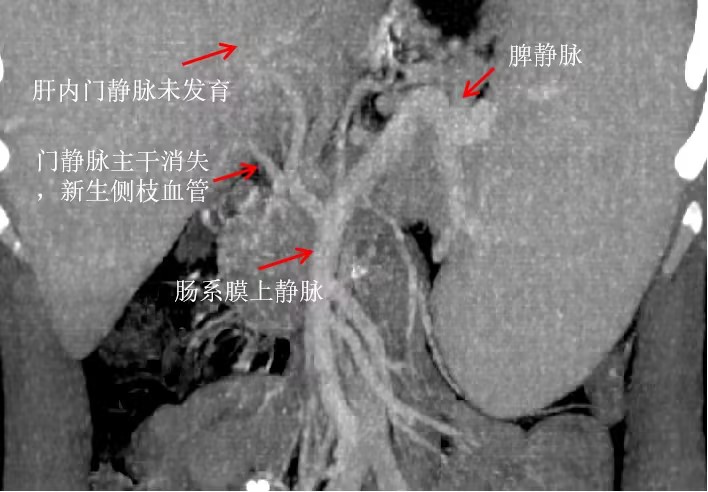

北京清华长庚医院4月7日电通讯员 郝华媛 周汐遥16岁的小佳曾是个充满活力、热爱运动的少年。然而,一次突如其来的晕倒,如同一道闪电,划破了他平静的生活。小佳被诊断出患有一种名为Abernethy综合征2的罕见病,全球仅有80余例报道。这种疾病不仅让他面临重度肺高压的威胁,还可能引发一系列危及生命的并发症,如食管胃静脉曲张出血、右心功能衰竭、肝肾综合征等。更令人揪心的是由于小佳肝脏内血流分布异常,他的肝脏内还生长着一个直径达13厘米的肿物,癌变的风险如影随形……

肝胆胰中心执行主任卢倩介绍,该疾病属于大血管畸形,面对小佳复杂的病情,手术团队必须在两个方面取得突破:一是重建已闭合的门静脉,二是确切封闭肝外分流血管。然而,最大的挑战还在于小佳的重度肺动脉高压。他的肺动脉压高达96mmHg已达常人的5-6,手术中发生右心衰竭的风险极高,这些也正是其他医院望而却步的主要原因。但清华长庚的专家们并未退缩,卢倩带领副主任医师徐光勋、主治医师于里涵组织了麻醉科、心脏外科、肝脏ICU心血管内科、呼吸与危重症医学科、血管外科等多学科专家多次进行会诊和术前讨论。包括手术方案、麻醉准备、术中紧急用药及抢救措施、体外膜肺氧合ECMO路径、术后监护难点、肺动脉压用药等核心问题,经过专家们共同研究,为围手术期风险点制订了详尽的处置应急预案。

多学科联合保驾,患者与家属的充分信任,为这台高危肝移植手术注入了底气。术中,卢倩发现小佳的门静脉肝外主干已经全部闭塞,从消化道返回肝脏的血液流动收到阻碍,需要将胰腺游离,在更深的位置探查肠系膜静脉和脾静脉,找到健康的血管做手术重建,相当于在大山深处开掘隧道并铺设铁路;而肝外的分流血管,经过以往的手术操作,局部粘连像撒了胶水一样,理不清、分不开,但团队凭借坚定的信念和精湛的技术,一步步切除了病变的肝脏,缝合封闭了增生的分流血管,并成功植入了健康的捐献肝脏。当肝脏恢复血供,颜色逐渐转为正常,手术宣告成功。然而正如预期的那样,小佳出现了严重的右心功能衰竭。守候在旁的心脏外科副主任医师沈冬焱与麻醉科主任医师张欢当机立断,为他实施了ECMO,建立体外循环,把血引出体外,经过氧合处理后泵入体循环中,有效控制了右心负荷。经过20个小时的努力,小佳生命体征逐渐平稳下来